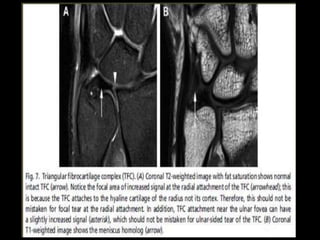

(a) Coronal T1 weighted image of the ankle demonstrates the tibiotalar joint (blue arrow) and

distal tibiofibular joint (red arrow). The osseous structures include the tibia (T), tibial plafond

(Tib Plaf), medial malleolus (MM), lateral malleolus (LM), talus (Tal), superior faces (SF), lateral

malleolar facet (LMF), medial malleolar facet (MMF), calcaneus (C), peroneal tubercle (PT), and

sustentaculum tali (ST). (b) Sagittal T2 weighted image again demonstrates the tibiotalar joint

(blue arrow), as well as the subtalar joint (yellow arrow). The talus to include the head (TH),

neck (TN), and body (TB) are noted, as well as the calcaneus (C).